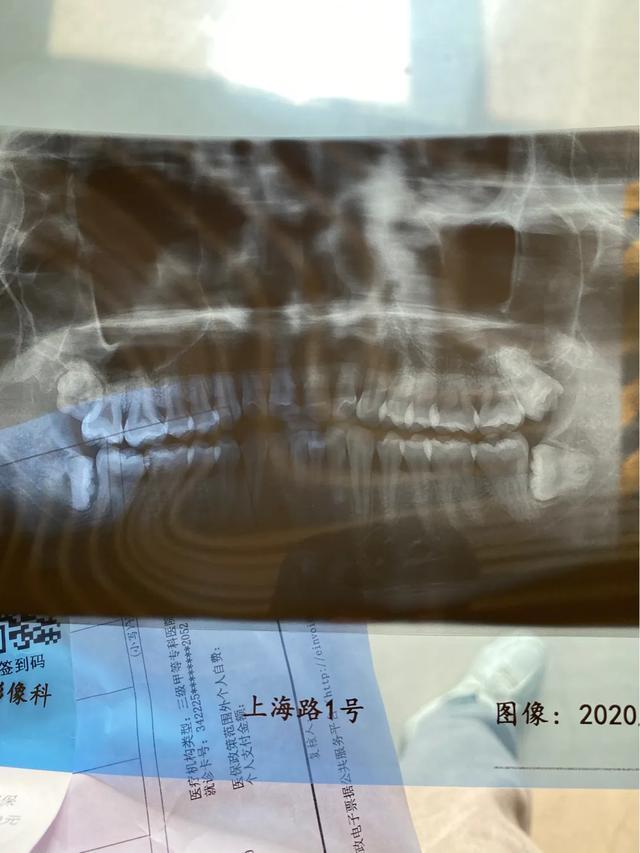

微信预约挂号 到现场一定要提前 不然人超级多 排队等叫 然后拍片 医生看完 3颗阻生齿 一颗已经长出来了 跟我说需要住院 填写了一下住院申请 回家等通知